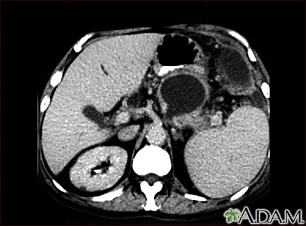

Pancreatic pseudocyst - CT scanBackPancreatic pseudocyst - CT scanA CT scan of the upper abdomen showing a pseudocyst in the corpus, or tail, of the pancreas. E-mail FormEmail ResultsName:Email address:Recipients Name:Recipients address:Message: